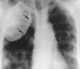

Oleothorax

Extrapleural plombage

Pleural calcification